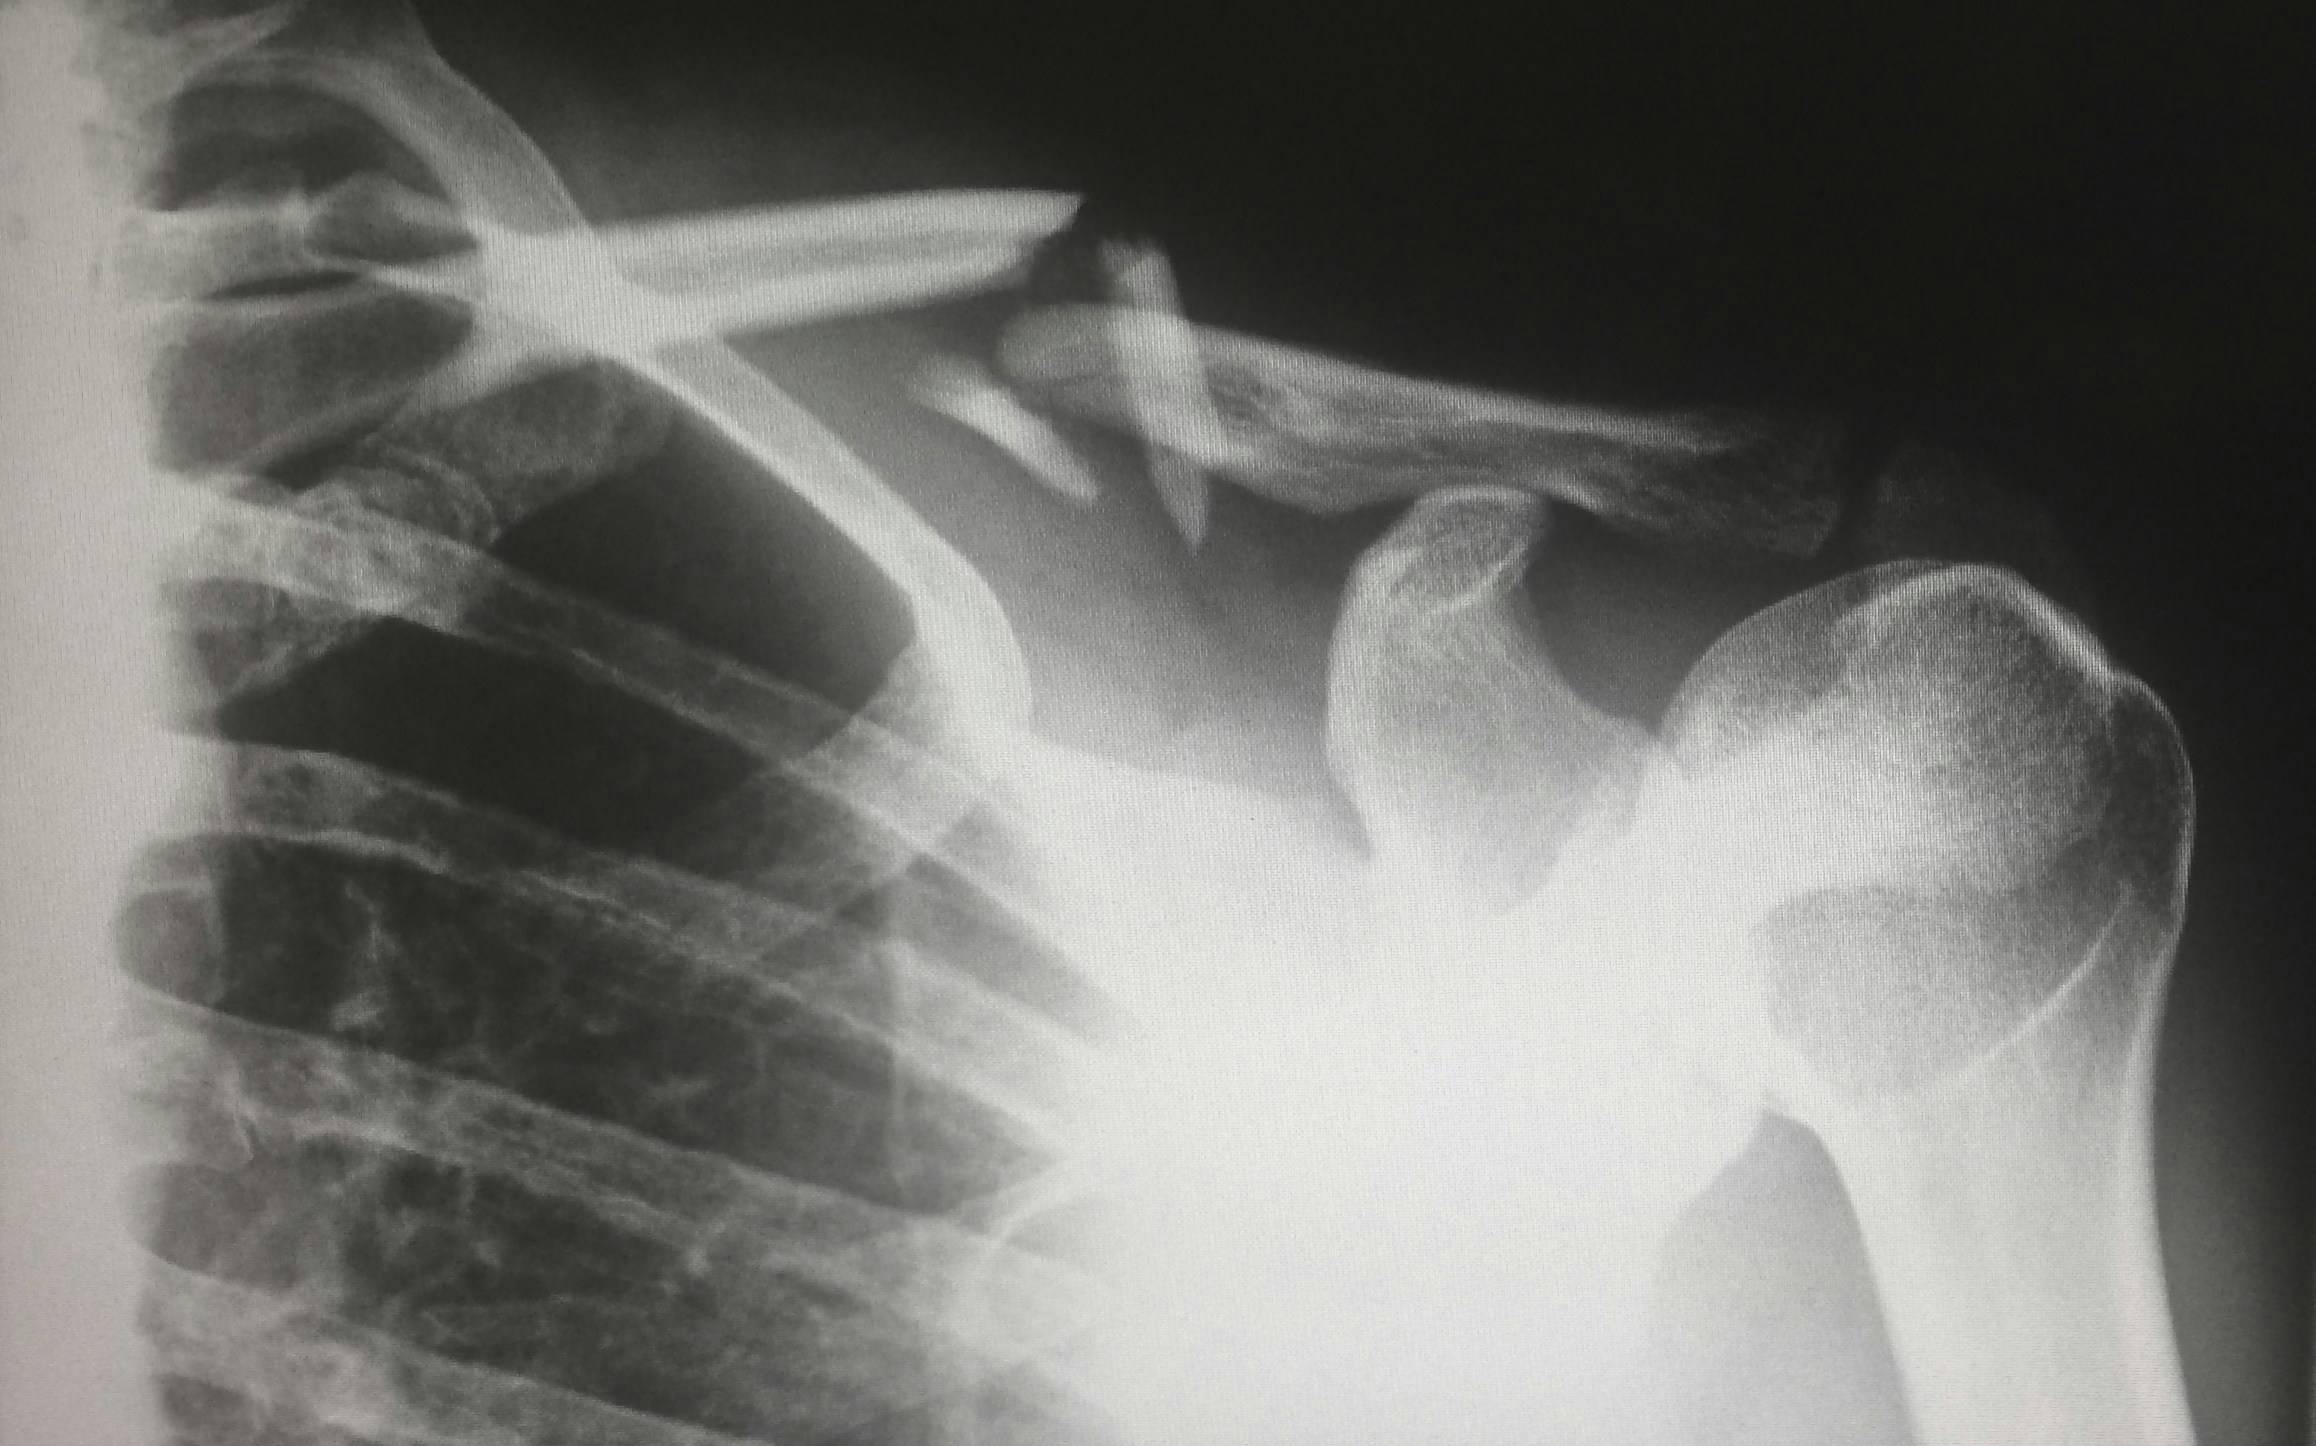

Bestätigt das Röntgenbild die Fraktur, stellt sich die Frage: Konservativ behandeln oder doch operieren? Bis vor kurzer Zeit wurden die meisten Brüche mit einem sogenannten Rucksackverband behandelt. Bei diesem Verband wird die Schulter durch ein spezielles Verbandsystem so nach hinten gezogen, dass das Schlüsselbein in Position bleibt und gerade zusammenwachsen kann. Bei einfachen, glatten Brüchen dauert es dann bis zu sechs Wochen, bis der Arm schon wieder leicht bewegt werden kann. Leichtes Training, das die Schulter nicht belastet, ist erst nach zehn bis zwölf Wochen wieder möglich. Heute wird der Verband auch weggelassen, wenn der Bruch sehr einfach ist – oft ist die Heilung dann ohne Verband genauso schnell wie mit Verband.

Kompliziertere Frakturen werden heute eher operiert – dazu wird das Schlüsselbein durch Platte und Schrauben zusammengehalten, die später auch wieder operativ entfernt werden müssen. In der Regel ist die Heilung nach einer OP etwas schneller – immer abhängig von der Komplexität des Bruches und anderen Verletzungen rund um die Fraktur. Dort verlaufen viele Nerven und Gefäße, die durch den Sturz ebenfalls beschädigt werden können.